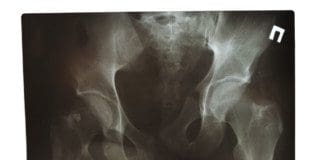

Getting to the root cause of any symptoms that are presenting and addressing them is essential before the body can be at its optimum. A common root cause of pain, low energy, and various general health complaints is spinal misalignment. Poor spinal alignment leads to poor nerve energy flow and poor blood circulation. When the body and nervous system function incorrectly, there is interference with the body’s ability to process normal functions that leads to various forms of dysfunction. A chiropractor can recognize the smallest of changes in the spine that could be affecting the body’s health.